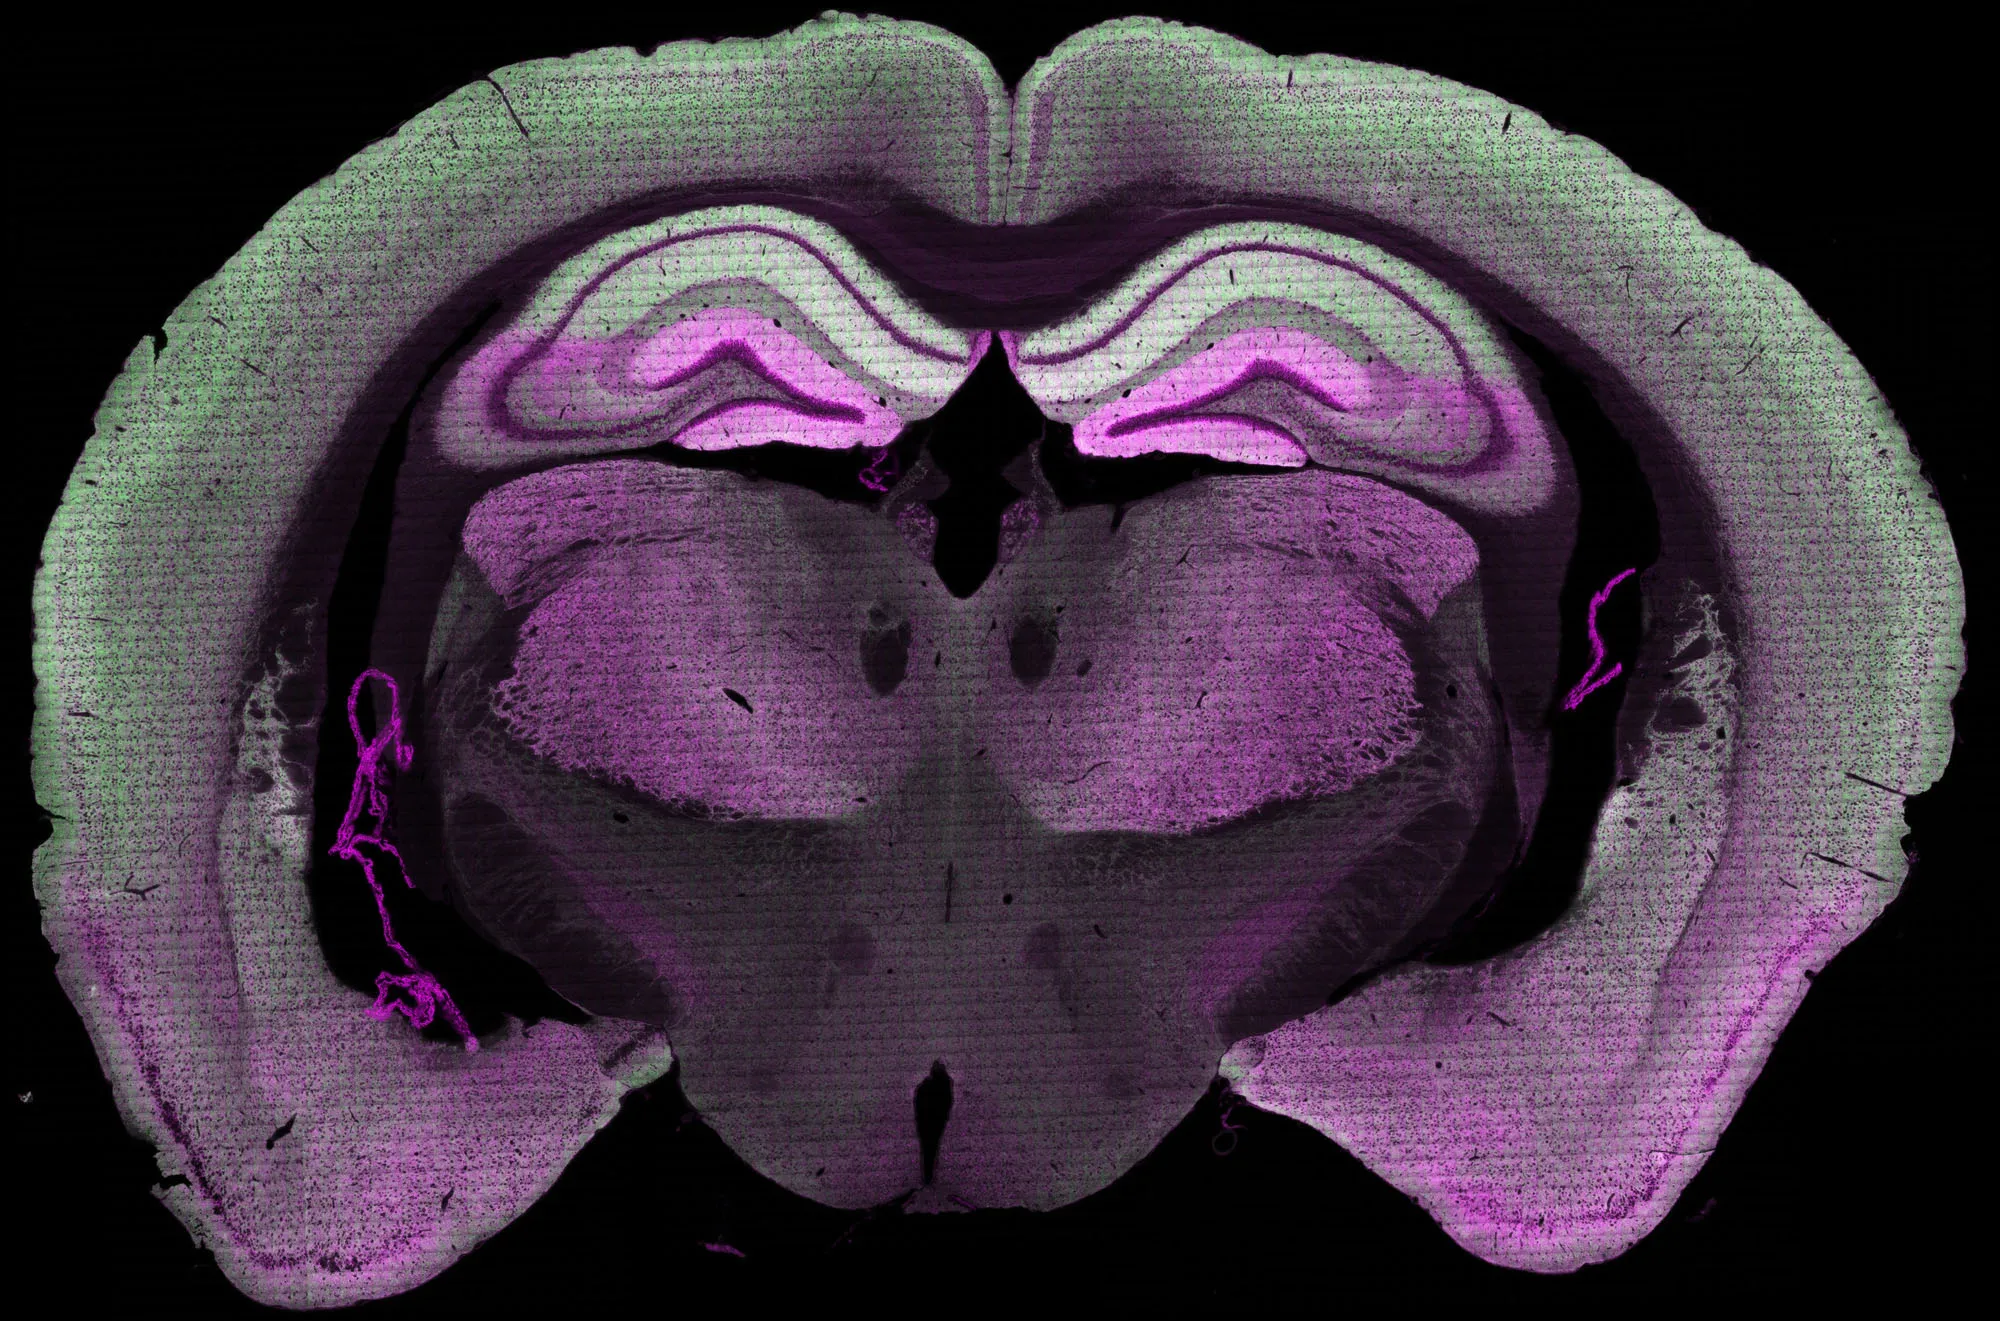

Mouse brain segment showing distribution of two synapse proteins

Mouse brain segment showing distribution of two synapse proteins. Credit: The University of Edinburgh.

The team studied sections of brain tissue engineered to emit light, allowing the scientists to see individual synapses in colour. By tagging distinct types of molecules in each synapse by colour, they were able to detect a vivid pattern of synapses across the brain. Different groups of synapses were active depending on distinct behaviours of the mice – such as feeding, running and jumping. The diversity of synapse types may be key to recalling information, helping the brain to quickly locate memories through patterns of its activity. This finding could help scientists understand more about how memory problems develop.